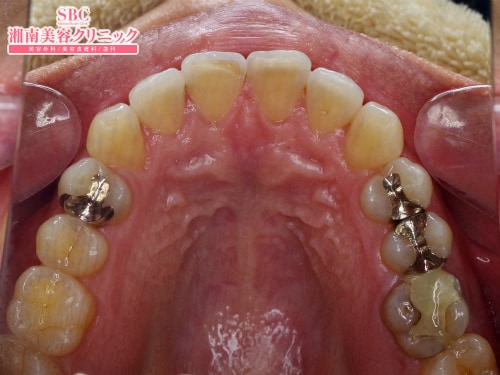

施術前

湘南歯科グループ唯一の技術指導医審美・美容歯科経験西日本No.1歯科西エリアマネージングドクター経験・診断・技術に基づいた本物の施術をご提供致します。マウスピース矯正=インビザラインGOの症例です。術前のガタつきの目立つ前歯。この歯並びをマウスピースを1日20時間以上装着する事で改善。ガタつき整いました。

マウスピース矯正=インビザラインGOの症例です。

術前のガタつきの目立つ前歯。

この歯並びをマウスピースを1日20時間以上装着する事で改善。

ガタつき整いました。